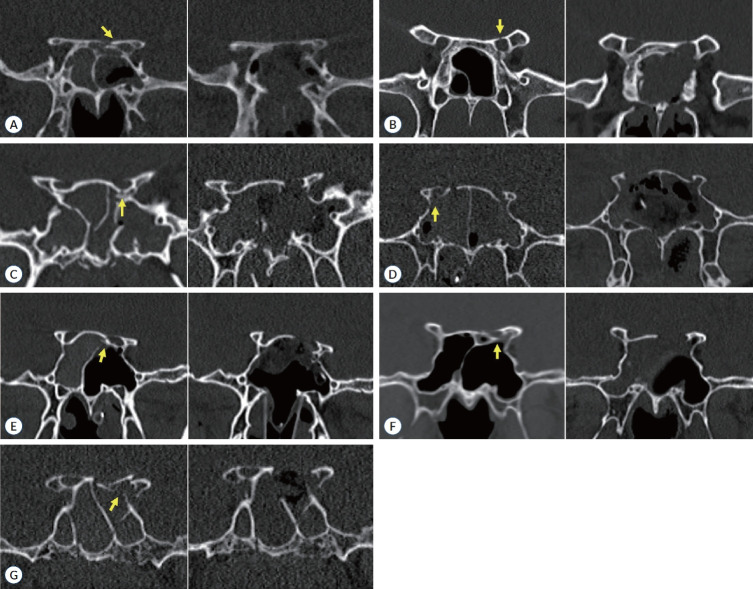

目的:创伤性视神经病变(TON)是指视神经受到直接或间接损伤而引起的一种病理状态。对于脑外伤患者而言,由于精神状态的改变,很多情况下很难对视力进行充分评估。为了解决这一问题,我们研究了TON患者术前瞳孔对光反射作为视神经减压术后手术效果预测因素的情况:方法:2020 年 4 月至 2022 年 9 月,我们招募了在我院确诊为 TON 并接受内窥镜视神经减压术的患者。手术前后由眼科医生进行视力和瞳孔反射测试:结果:共招募了七名患者。他们的年龄从 9 岁到 78 岁不等,均为男性。在这 7 名患者中,手术前瞳孔对光反射为 6 毫米(迟钝)和 7 毫米(固定)的患者视力没有改善。术前对直接反射或对侧间接反射测试有一定反应的患者术后视力有所改善:结论:直接和间接瞳孔反射是决定治疗瞳孔强直的重要因素。对于视神经管骨折的昏迷患者,根据瞳孔反射进行及时的手术干预可以防止永久性视力丧失。

Results: Seven patients were enrolled. Their ages ranged from 9 to 78 years and all were male. Among the seven patients, the patient whose pupillary light reflex was sluggish with 6 mm-sized pupil and absent with 7 mm-sized pupil before surgery showed no improvement in vision. Patients with some response to direct reflex or contralateral indirect reflex testing preoperative showed vision improvement after operation.